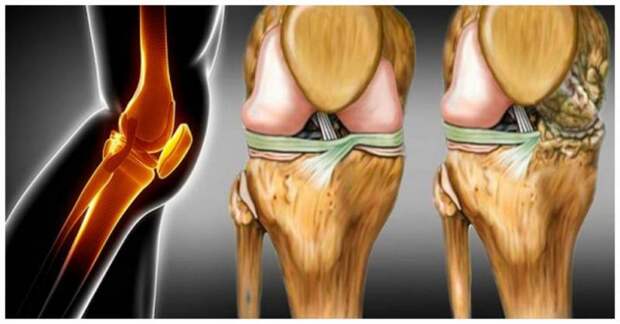

Чаще всего повреждения в тканях происходят на фоне возрастных изменений, а также из-за травм (как правило, спортивных). В этом случае люди начинают испытывать довольно сильные боли в пораженной области, им становится сложнее двигать верхними и нижними конечностями. Если в такой ситуации человеку не оказывается специализированная помощь, то это может привести к еще большему изнашиванию суставов. Из-за этого на руки и ноги будут оказываться слишком сильные нагрузки. Без вспомогательных средств регенерация хрящевой ткани становится невозможной и человек рискует заполучить более серьезные осложнения.

Особенности восстановления

В первую очередь стоит сказать, что хрящевая ткань являются довольно хрупкой субстанцией, которую можно без проблем повредить и нанести организму вред. Если человек неправильно будет распределять нагрузку или повышать ее, то это только ухудшит его состояние. Именно поэтому не стоит заниматься самолечением, а лучше обратиться к специалисту.

Как правило, для того, чтобы восстановить нормальную хрящевую ткань в суставах, необходимо принимать хондопротекторы. Наиболее эффективными данные средства будут в том случае, если человек обратился за помощью на начальной стадии заболевания суставов. Если речь идет о запущенной форме недуга, то, говоря о том, можно ли восстановить хрящевую ткань в суставах в этом случае, вероятнее всего ответ будет отрицательным. В такой ситуации способно помочь только хирургическое вмешательство. При помощи медикаментозной терапии подобные проблемы будет решить достаточно сложно. Поэтому не стоит дотягивать до последнего и прибегать к более серьезным процедурам.